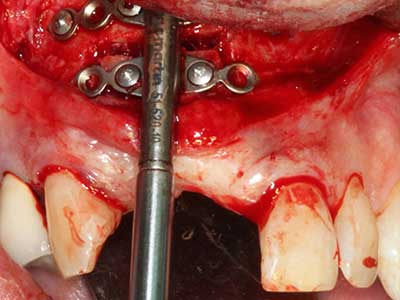

Костната тъкан е не само минерализирана структура, тя съдържа и съществено количество колагенови влакна. Това означава, че тя има не само добра компресивна сила, но и известна степен на гъвкавост, която може да се възприеме като предимство при извършване на костна аугментация. В класическата процедура по разширяване чрез костно разделяне, атрофиралият алвеоларен гребен е разделен надлъжно и внимателно разширен след достигане на подходящата остеотомна дълбочина (Фиг. 13-16), в идеалния случай без допълнително отстраняване на периостеума (Brugnami, Caiazzo et al. 2014, Stricker, Fleiner et al. 2014). Системите с винт и пластини с увеличаване на разстоянието при разширяване са доказали ефективността си при разделяне на двете костни ламели, оставайки под прага на фрактурите. В общи линии, оставащата ширина на костта от поне 3–4 mm е задължителна (Chiapasco, Zaniboni et al. 2006), за да се гарантира добра гъвкавост и достатъчно костно покритие за бъдещото поставяне на импланти. Ако е необходимо, вертикалната остеотомия на едната или двете страни може да подобри гъвкавостта. Комбинацията с допълнителни техники за аугментация, особено в букалната страна, е описана като алтернатива на класическата техника.

Процедурата по разделяне е атравматична и няма голяма загуба на пространство, използвайки пиезотриони, и няма значителна разлика между импланти в разделени челюсти и импланти в алвеоларния гребен без костен дефицит (Chiapasco, Zaniboni et al. 2006, Danza, Guidi et al. 2009). Въпреки това, важно е да има достатъчно и продължително охлаждане, особено при ограничено и дълбоко разделяне, за да се избегне термичен стрес в апикално-остеотомните зони.